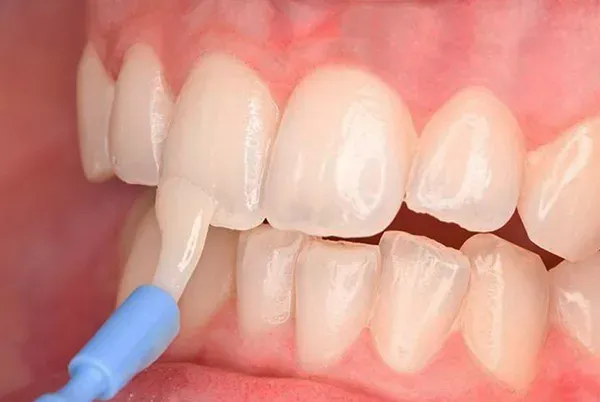

răng có mảng bám ố vàng là hiện tượng phổ biến mà nhiều người gặp phải, gây mất thẩm mỹ và có thể ảnh hưởng đến sức